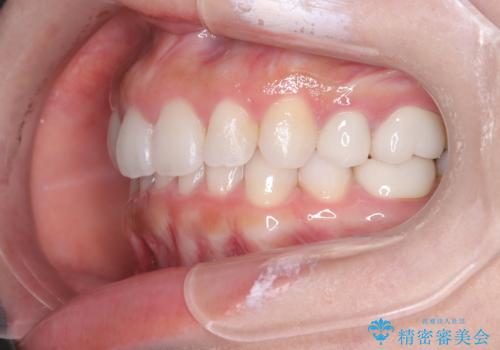

歯の中心のズレを解消し、より美しい口元へ

- 上下の歯の中心(正中)のズレと、口元の見た目を気にされて来院されました。精密な検査の結果、咬み合わせのバランスを整えながら、正中線を一致させる治療が必要と判断。患者様のご希望に合わせ、透明で目立ちにくいインビザライン(マウスピース矯正)による治療計画を立案しました。歯列全体を奥(遠心)へ移動させるためにゴムかけを併用。さらに、見た目を改善するため、既存の金属の被せ物をセラミッククラウンに交換することも治療計画に組み込みました。

今回の矯正治療では、透明なマウスピース型の装置インビザラインを使用しました。歯列を奥へ動かす遠心移動の効率を高めるため、患者様ご自身にゴムかけも行っていただきました。この併用によって、歯をより正確かつスムーズに動かすことができ、上下の歯の中心である正中線を一致させることが可能になりました。また、治療の最終段階では、以前から入っていた金属の被せ物を、天然歯に近い色合いのセラミッククラウンに交換。矯正治療と審美治療を組み合わせることで、機能的な咬み合わせの改善に加え、金属が見えない、より自然で美しい口元を獲得していただけました。